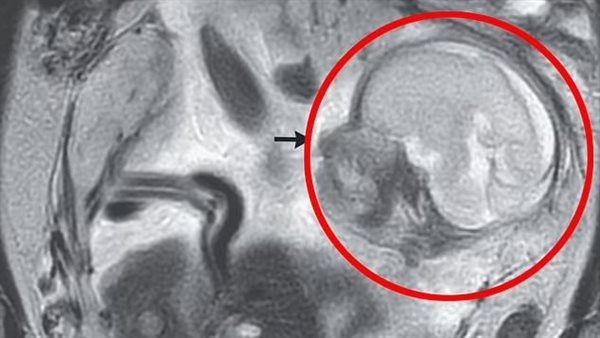

وذهبت البالغة من العمر 37 عامًا إلى الأطباء، وهي تشكو من ألم في بطنها استمر لـ 10 أيام، بالإضافة إلى الانتفاخ، الذي أصبح أسوأ تدريجيًا، قبل اكتشاف عمليات المسح أن الجنين طبيعي التكوين، كان ينمو في تجويف البطن، وهو الفضاء بين المعدة والأمعاء.

وشخّص الأطباء إصابتها بالحمل في البطن، وهو نوع من الحمل خارج الرحم الذي يحدث في البطن، حيث كان الطفل في التجويف البريتوني، أو المنطقة التي تحتوي على الأعضاء الحيوية، وكانت المشيمة متصلة بأعلى الحوض.